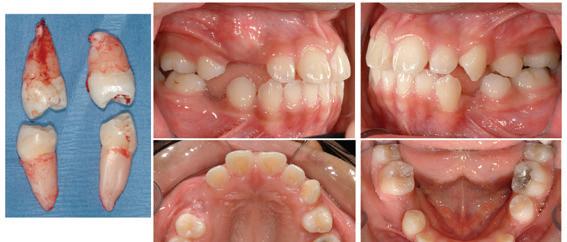

The non-extraction option was dismissed for numerous reasons, one of which was the patient’s increased skeletal vertical dimension and minimal overbite. Advancement of the incisors was contraindicated, and the transposition of teeth in the maxillary right quadrant remained a treatment planning dilemma. Extraction of teeth in the left quadrants only was a serious consideration, as it would not risk incisor advancement and bite opening to the same degree as the nonextraction option. It would resolve the mandibular crowding, correct the left Class III canine relationship, and reflect the INITIAL right midline deviation. Once again however, this unilateral left extraction option did not eliminate the transposition treatment planning dilemma. Only one plan did, Option 3. Extraction of tooth #5 would permit tooth #6 to erupt and definitively solve the transposition. It would make the case the most predictable and time efficient. Photos (Figure 5) were obtained shortly after extracting the following teeth: 5, 13, 21, and 29.

Figure 5: Photographs after extraction

.018 traditional twin brackets were placed on all of the maxillary teeth following the extraction procedure by the referring general dentist. Particular attention was placed on proper bracket placement for distal root angulation of tooth #12 (Figure 6). Brackets were placed on the mandibular teeth shortly thereafter. In this way, the source of any inadvertent bite opening could be targeted. Round nickel titanium arch